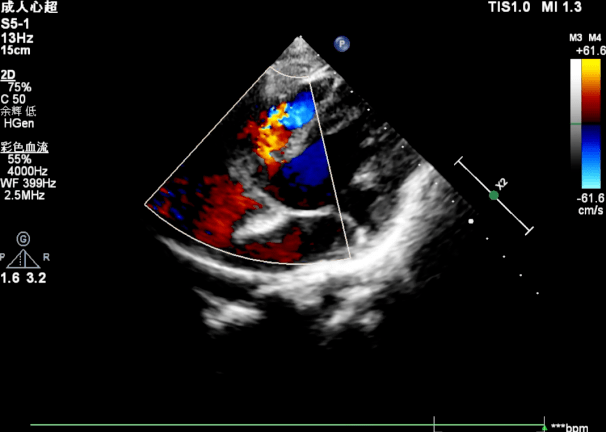

华南首例|张智伟教授,汪周平教授于广州妇女儿童医疗中